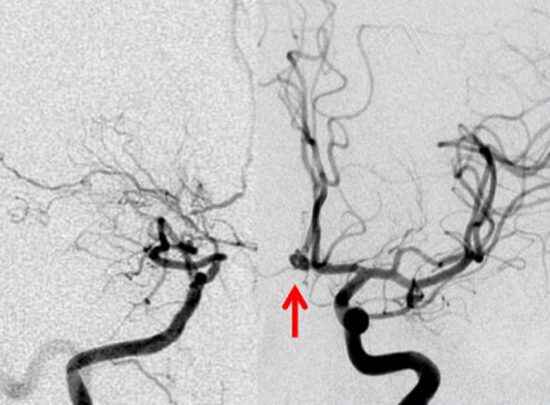

小児のクラニオ:放射線治療後の内頸動脈閉塞と脳動脈瘤の発生

4歳の時に頭蓋咽頭腫に対して50グレイの分割照射を受けました。両側の内頸動脈と前交通動脈が被曝しています。16歳(12年後)に左片麻痺の虚血発作を生じました。右内頸動脈が閉塞してウィルス動脈輪閉塞(モヤモヤ病)になっていました。前交通動脈に動脈瘤(赤矢印)もできていました。小児の頭蓋咽頭腫への放射線治療ではかなり高率に閉塞性脳血管障害を生じるのですが,治療後10年以上がたってから起るので,治療を行った医師はそれをみることはほとんどありません。